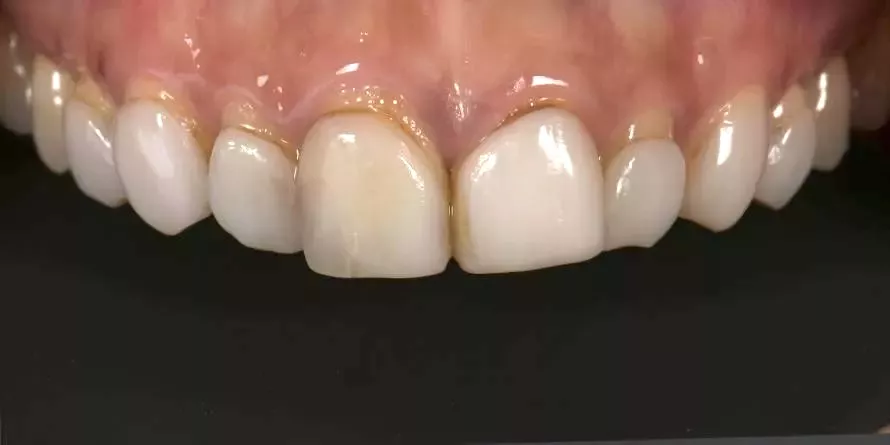

因此,每一次的治療,我都傾注最大的心力,在品質及細節上堅守高標準,讓成果真正經得起考驗。

一副笑容的改變,帶來的不只是外觀的提升,更深刻影響一個人在職場、人際與生活中的自信。相反的,一顆做得不夠好、撐不久的牙齒,或許短期內無痛無礙,卻會在無形中逐漸消磨一個人對生活的底氣。